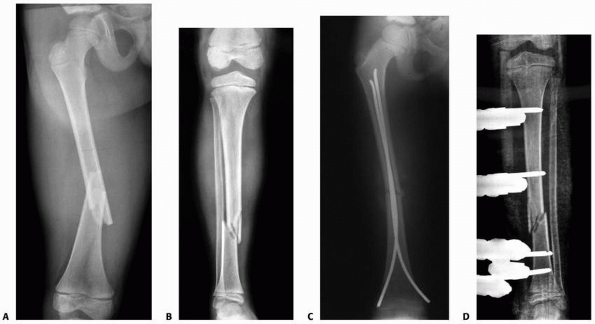

including spasticity, a floating knee, multiple long-bone fractures, an

flexible intramedullary nails (Figs. 25-22 and 25-23).